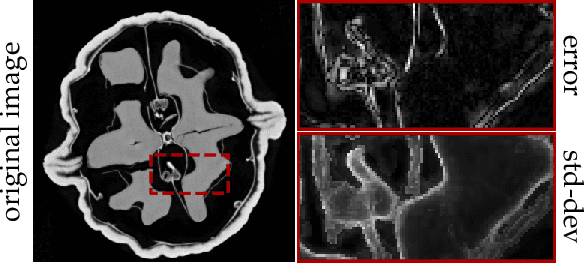

Abstract:Existing deep-learning based tomographic image reconstruction methods do not provide accurate estimates of reconstruction uncertainty, hindering their real-world deployment. To address this limitation, we construct a Bayesian prior for tomographic reconstruction, which combines the classical total variation (TV) regulariser with the modern deep image prior (DIP). Specifically, we use a change of variables to connect our prior beliefs on the image TV semi-norm with the hyper-parameters of the DIP network. For the inference, we develop an approach based on the linearised Laplace method, which is scalable to high-dimensional settings. The resulting framework provides pixel-wise uncertainty estimates and a marginal likelihood objective for hyperparameter optimisation. We demonstrate the method on synthetic and real-measured high-resolution $\mu$CT data, and show that it provides superior calibration of uncertainty estimates relative to previous probabilistic formulations of the DIP.